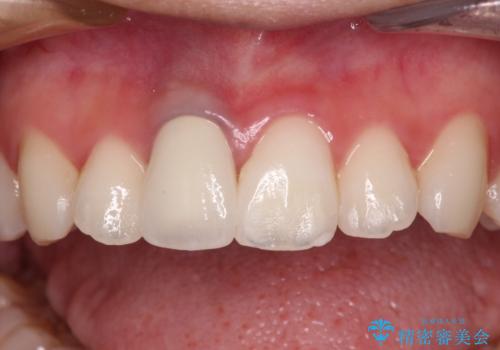

- 虫歯により神経を取り除いた前歯の変色が気になるとのことで来院された患者様です。

レントゲン写真より、歯根の炎症が認められなかったため、ファイバーコアによる土台築製後、オーダーメイドタイプのオールセラミッククラウンにて補綴することとしました。